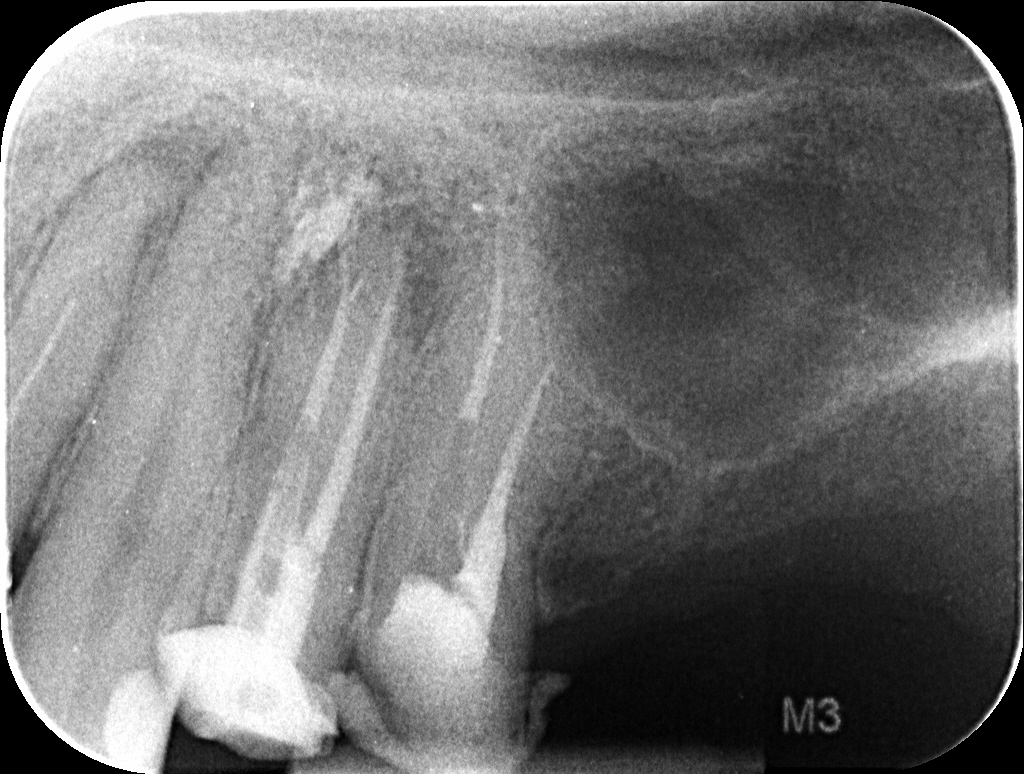

Il piano di cura proposto al paziente prevede il ritrattamento e la ricostruzione adesiva dell’elemento 25 e la successiva copertura cuspidale tramite restauro indiretto. Previa anestesia plessica si esegue l’isolamento dell’elemento mediante diga di gomma. La rimozione del restauro coronale viene eseguita con frese diamantate e abbondante irrigazione. Ultimata questa fase risultano ben visibili i perni in fibra di carbonio cementati nei canali palatale e vestibolare. La rimozione di questi ultimi viene eseguita mediante manipolo ultrasonico con inserto Start-X N.3 (Dentsply-Sirona) consumando i perni stessi e distaccando il cemento composito presente nel canale (Figure 2-3).